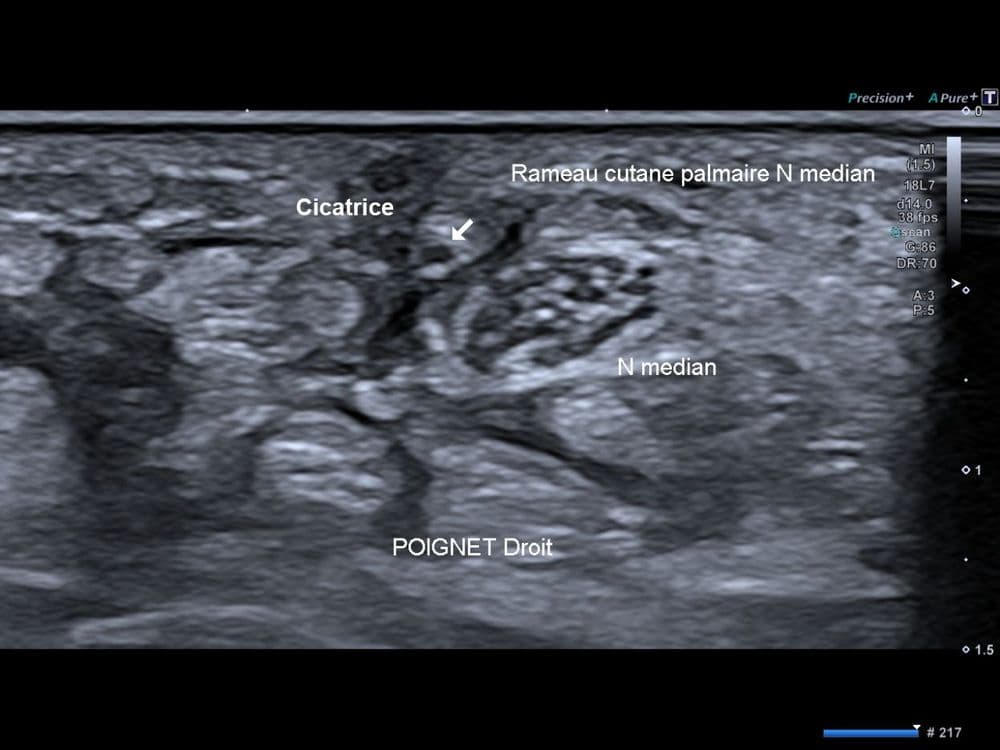

Anesthésie localisée à la partie proximale de la paume de la main dans les suites d'une ostéosynthèse radiale.

US